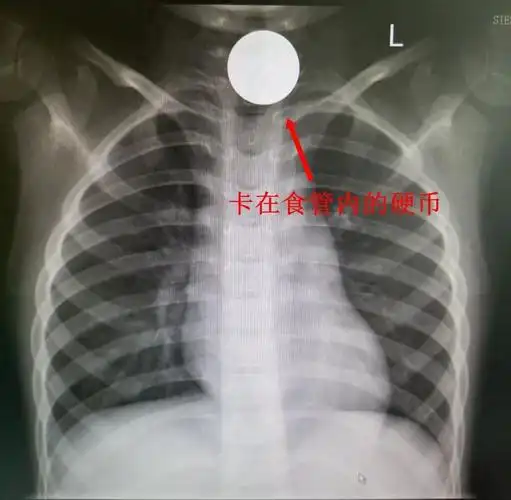

2分钟兰人医消化内科为三岁幼童取出食管异物

异物嵌顿于患儿食管内

颈段的食管有点肿胀,当时只是高度怀疑食道异物,所以就住院治疗.

幼儿误吞硬币入食管,医生"取钱有术"_误吞异物

项城市中医院消化内科之内镜室 4岁儿童食管异物成功取出术 胡道达